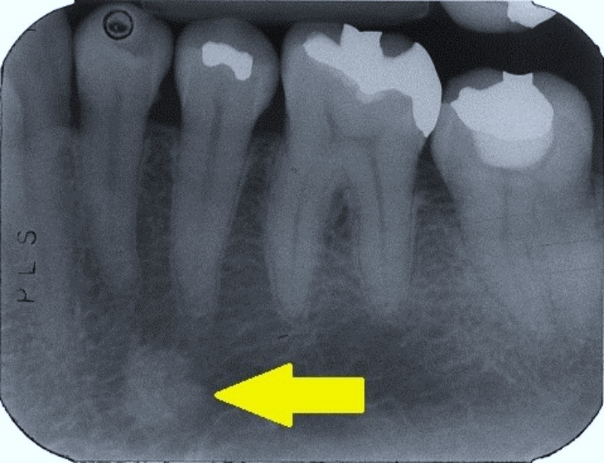

19. (Select ONE correct answer)

What is the most likely diagnosis for the entity shown by the arrow?